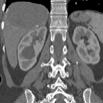

Mass Measurements

在横断位.冠状位.矢状位上分别测量mass的最大径线以及mass的体积测量:

Axial Dmax = 102.9 mm

Coronal Dmax = 100.2 mm

Sagittal Dmax = 80.8 mm

体积:267.467 cm3

Mass to neighboring arteries distances

到腹部各邻近重要血管的最小距离

To 肝右动脉: 9.5 mm

To 肝总动脉: 58.7 mm

To 腹腔动脉: 45.4 mm

To 右肾动脉: 26.8 mm

To 胆囊动脉: 85.6 mm

To 脾动脉: 72.2 mm

To 肠系膜上: 58.6 mm

Mass to neighboring bones/organs distances

到各邻近骨骼及脏器的最小距离

To 右肾: 1.0 mm

To 肋骨:0 mm

To 腰椎:1.5 mm

To 体表皮肤:89.9 mm

To 胃小弯:58.9 mm